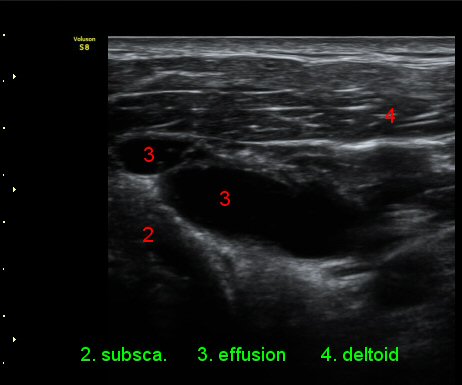

ŽÃÊÀÚ¸¦ ¾à°£ ´Ù¸®ÂÊ, ³»ÃøÀ¸·Î À̵¿ÇÏ´Ï °ß°©ÇÏ±Ù°Ç Ç¥Ãþ¿¡ ¸¹Àº ¾çÀÇ ¼ö¾×Àú·ù°¡ °üÂûµÈ´Ù(»çÁø 3).

ÆÈÀ» ¿ÜȸÀüÇÏ´Ï °ß°©ÇÏ±Ù°Ç Ç¥ÃþÀÇ ¼ö¾×Àú·ù°¡ ´õ¿í È®½ÇÇÏ°Ô °üÂûµµ´Ï´Ù(»çÁø 4).